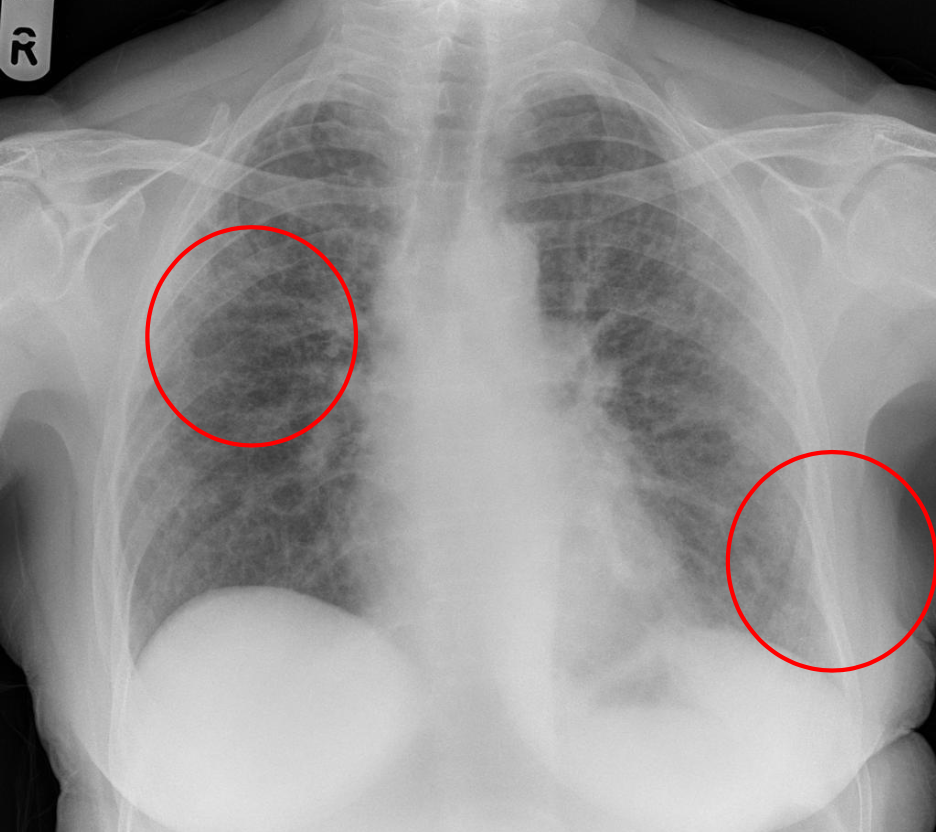

Rx para TEP

* Atelectasias basales * Elevación del diafragma * Joroba de Hampton * Signo de Westmark (aumento de lucidez = se ve más negro) * Dilatación de arteria pulmonar

¿Qué es el signo de westermark?

Hiperlucencia periférica (por oligoemia)

Signo de Westermark = TEP